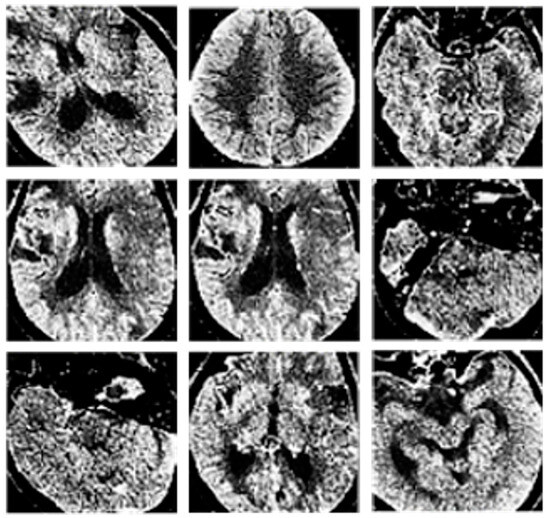

A comparison between the CT image processing that can be achieved through image enhancement methods and the original CT image is shown in Figure 2. Specifically, Figure 2a represents the original image, while Figure 2b represents the artifact image after feature enhancement.

The comparison between the original and enhanced image shows that the proposed image enhancement method can effectively extract artifact region information while weakening irrelevant region information such as bones, providing data support for the subsequent classification task.

Figure 2. Comparison of enhanced and initial image. (a) represents the original image, while Figure (b) represents the artifact image after feature enhancement.